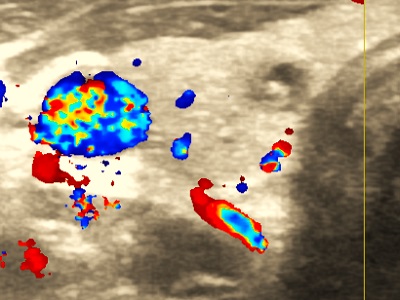

Węzły chłonne, guzki, przepukliny

Wykrywanie chorób powodujących powiększenie węzłów chłonnych. Guzki podskórne. Badanie zawartości przepuklin.

USG węzłów chłonnych-pozapalna limfadenopatia.